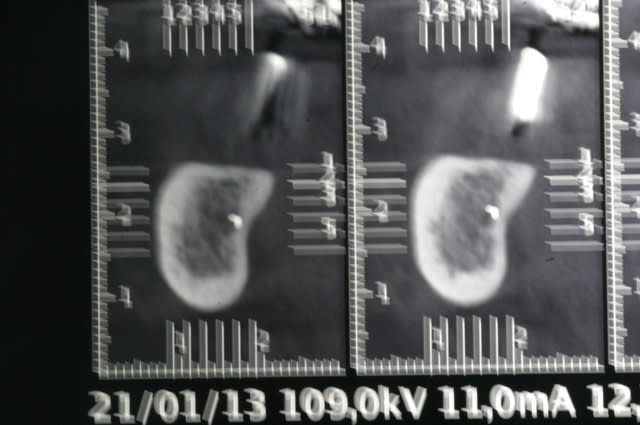

voila, j’espère que c'est lisible.

sans aucun problème, c'est un bon cas pour commencer.

Par contredans ce genre d'exercice, c'est au spreader, pas au foret.

si je retrouve les radios j'ai un cas "sympa".